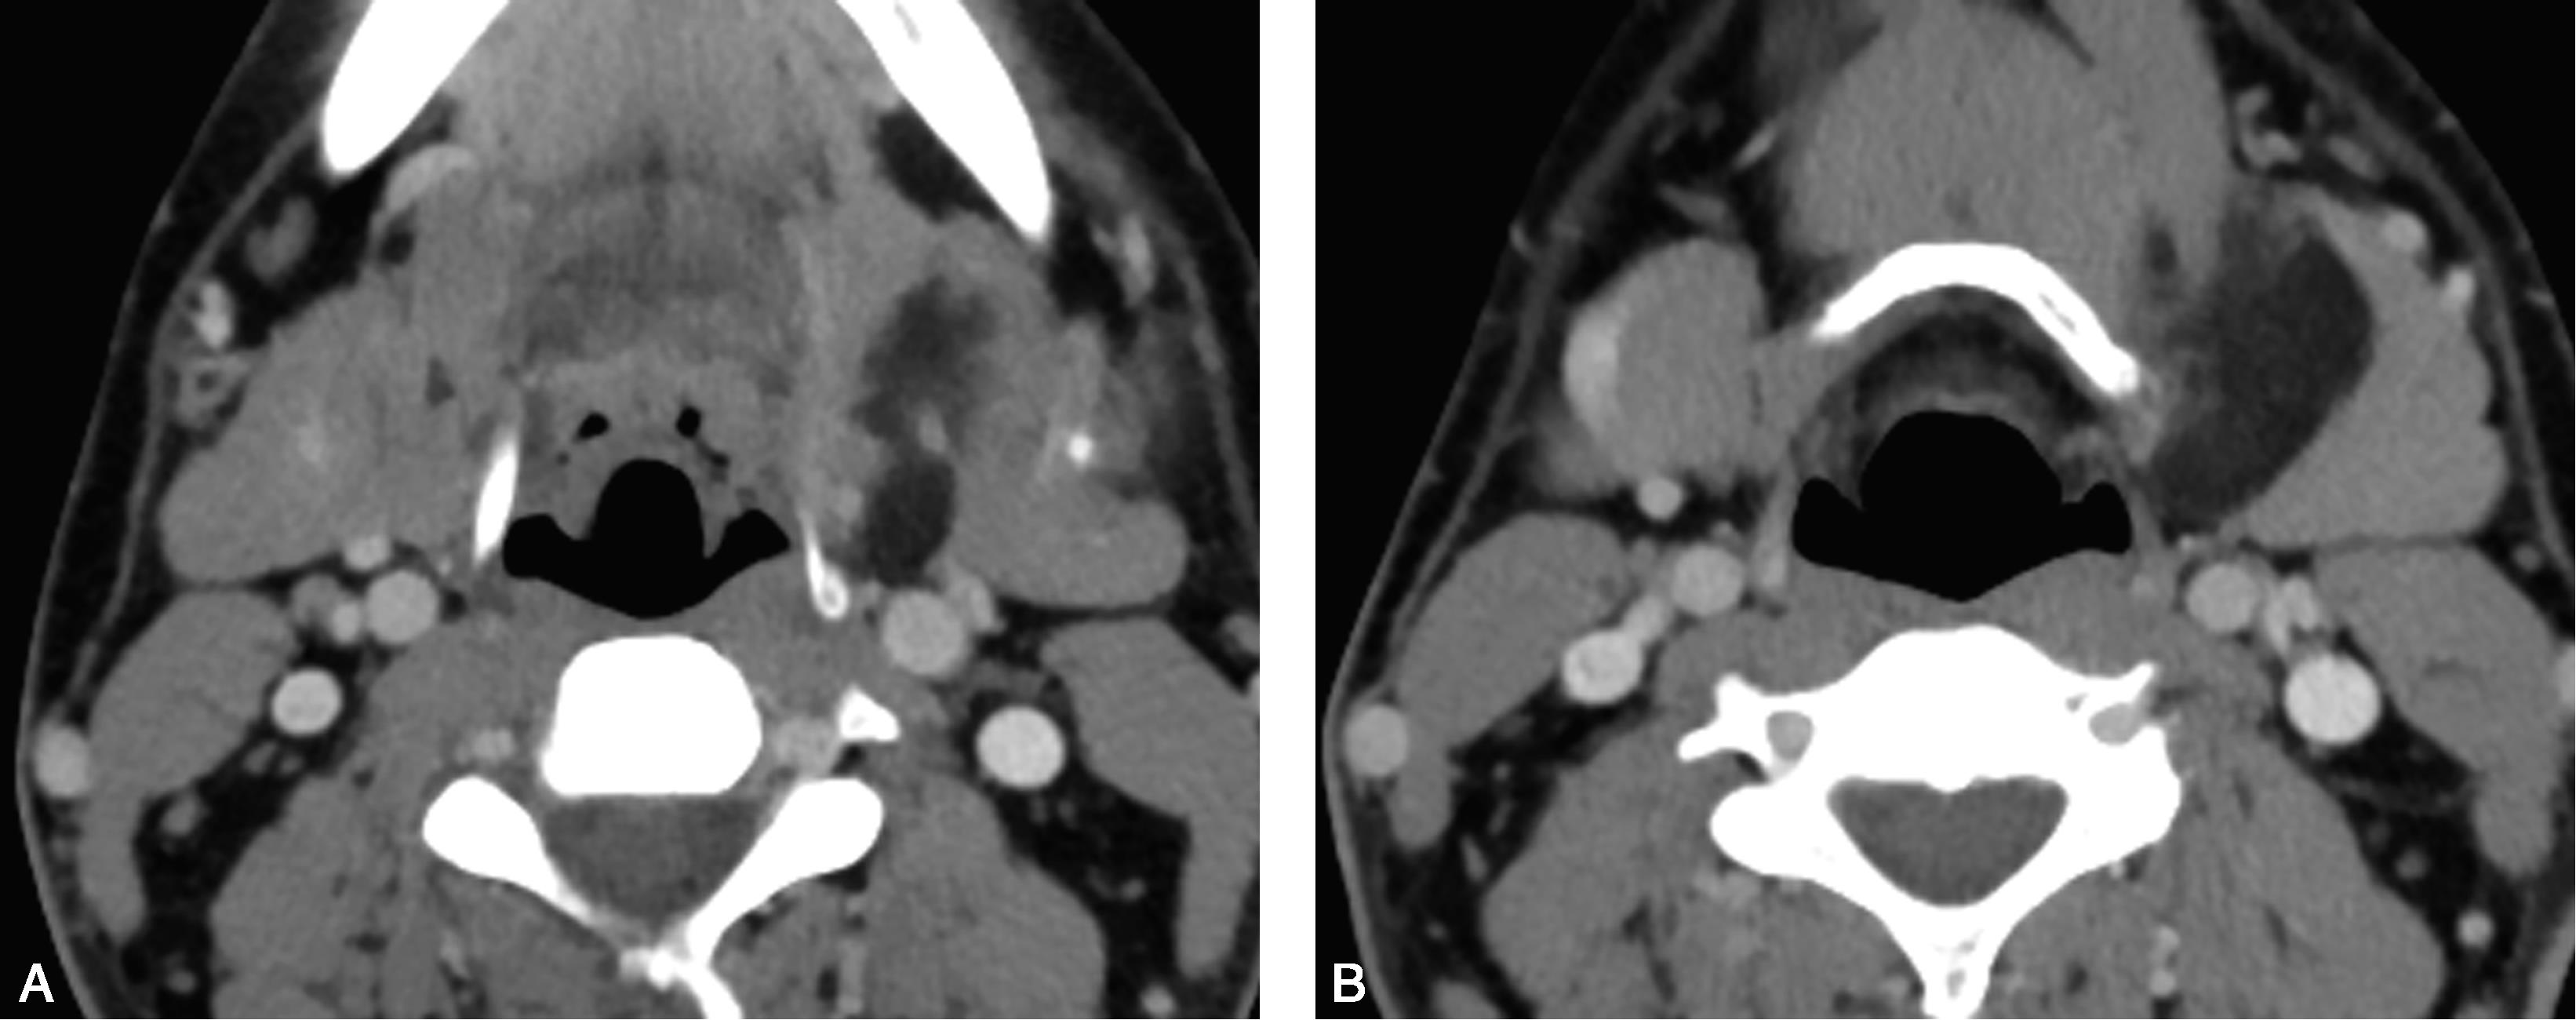

患者,女,10岁,偶然发现左侧颌下肿物半年(图5-5-3)。

图5-5-3 左侧颌下腺多形性腺瘤

MRI脂肪抑制轴位T

2

WI(图A)、冠状位(图G)及T

1

WI(图B)示左侧颌下腺内一类椭圆形异常信号,边界尚清晰,T

WI呈低信号,脂肪抑制T

WI呈混杂稍高信号;DWI(图C)呈不均匀高信号;ADC值局部略减低(图D);脂肪抑制增强T

WI(图E)示肿块明显不均匀强化;动态增强曲线(图F)呈持续上升型。